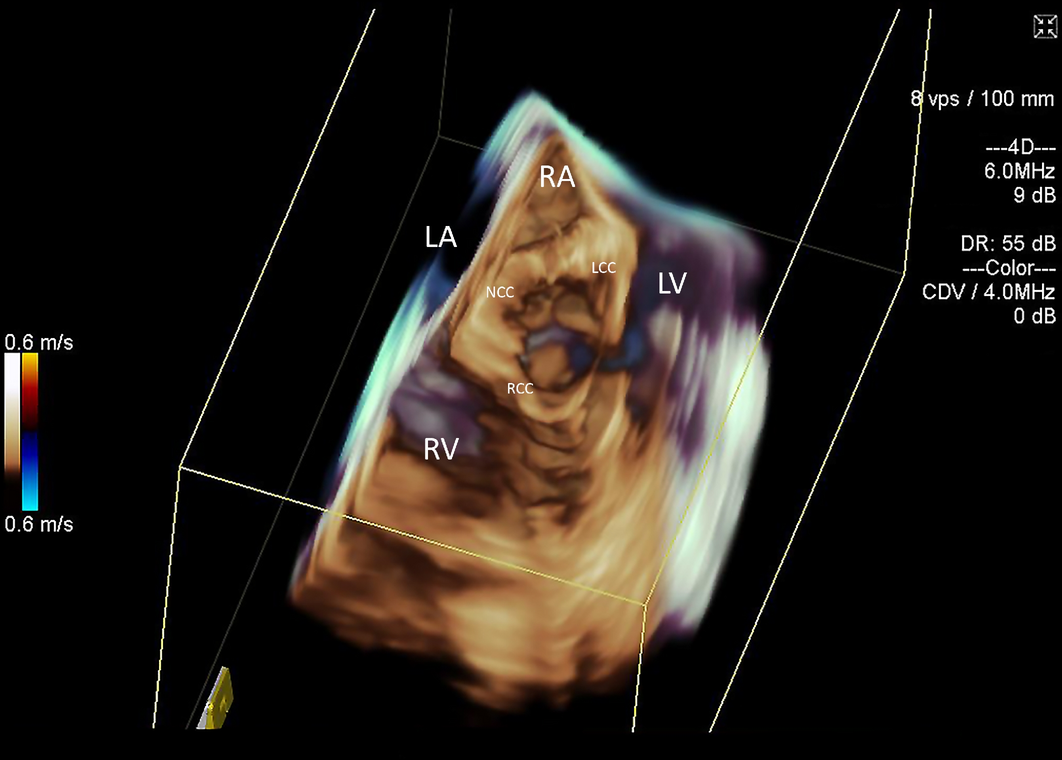

Implantation of Impella CP left ventricular assist device ...

Temporary circulatory support for cardiogenic shock - The Lancet